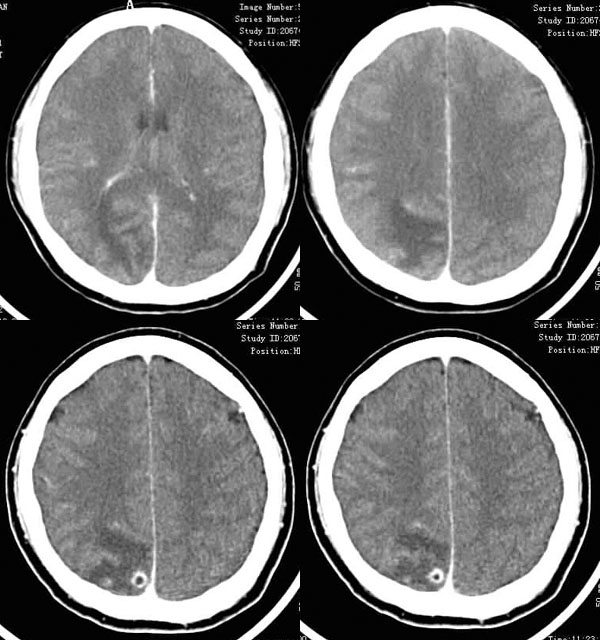

右顶叶病灶,呈规则的环状强化,周围有明显的水肿带,为典型的炎性肉芽肿表现。炎性肉芽肿可以为化脓性和结核性和由囊虫引起。

结核性肉芽肿近年病例增多,常常伴有其他部位的结核如肺结核,病灶多位于皮质区,中心常常为干酪样坏死,形成环状强化的表现,病程长者可见钙化。本例病变位于上矢状窦旁,非化脓性脑脓肿的好发部位,应该首先考虑结核性脑内肉芽肿。

皮质内小环形强化,环壁厚而光整,周围有明显水肿。考虑脑囊虫病。

ct平扫:右顶叶可见大片指状水肿,边缘不清,其内后部似有一小环形略高密度影。

增强扫描:指状水肿不强化,其内后部有一圆形厚壁强化环,内壁光滑,外壁较毛糙,占位不明显;余处示多发点条状强化。

结合临床,考虑右顶叶肉芽肿性病变。

需与胶质瘤,转移瘤区别,本例为年轻患者,慢性病程,实性成分较少,病灶散在多形强化,环影内密度较低,强化规则。建议做个胸片检查,可能会对诊断有利。

考虑脑tb,理由:1慢性发病2典型环行强化3指样水肿不象转移瘤那样明显4位于皮层下

与转

移瘤鉴别:1 老年2 多发 3 指样水肿明显,形成大水肿小瘤体样,甚至中线移位。4 一般强化壁较薄